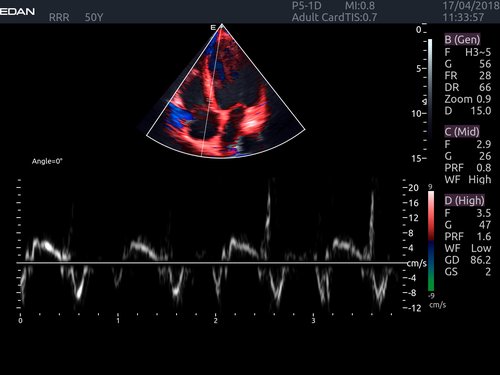

• Doppler: TAI passt sich dem Durchflusszustand an Verbesserte Kontinuität, Grenzerkennung und Ausfüllen

• Features: 3D, 4D, Farb/Doppler, Nadelführung, SW/B-Bild

• Echokardiographie

• Kardiologie